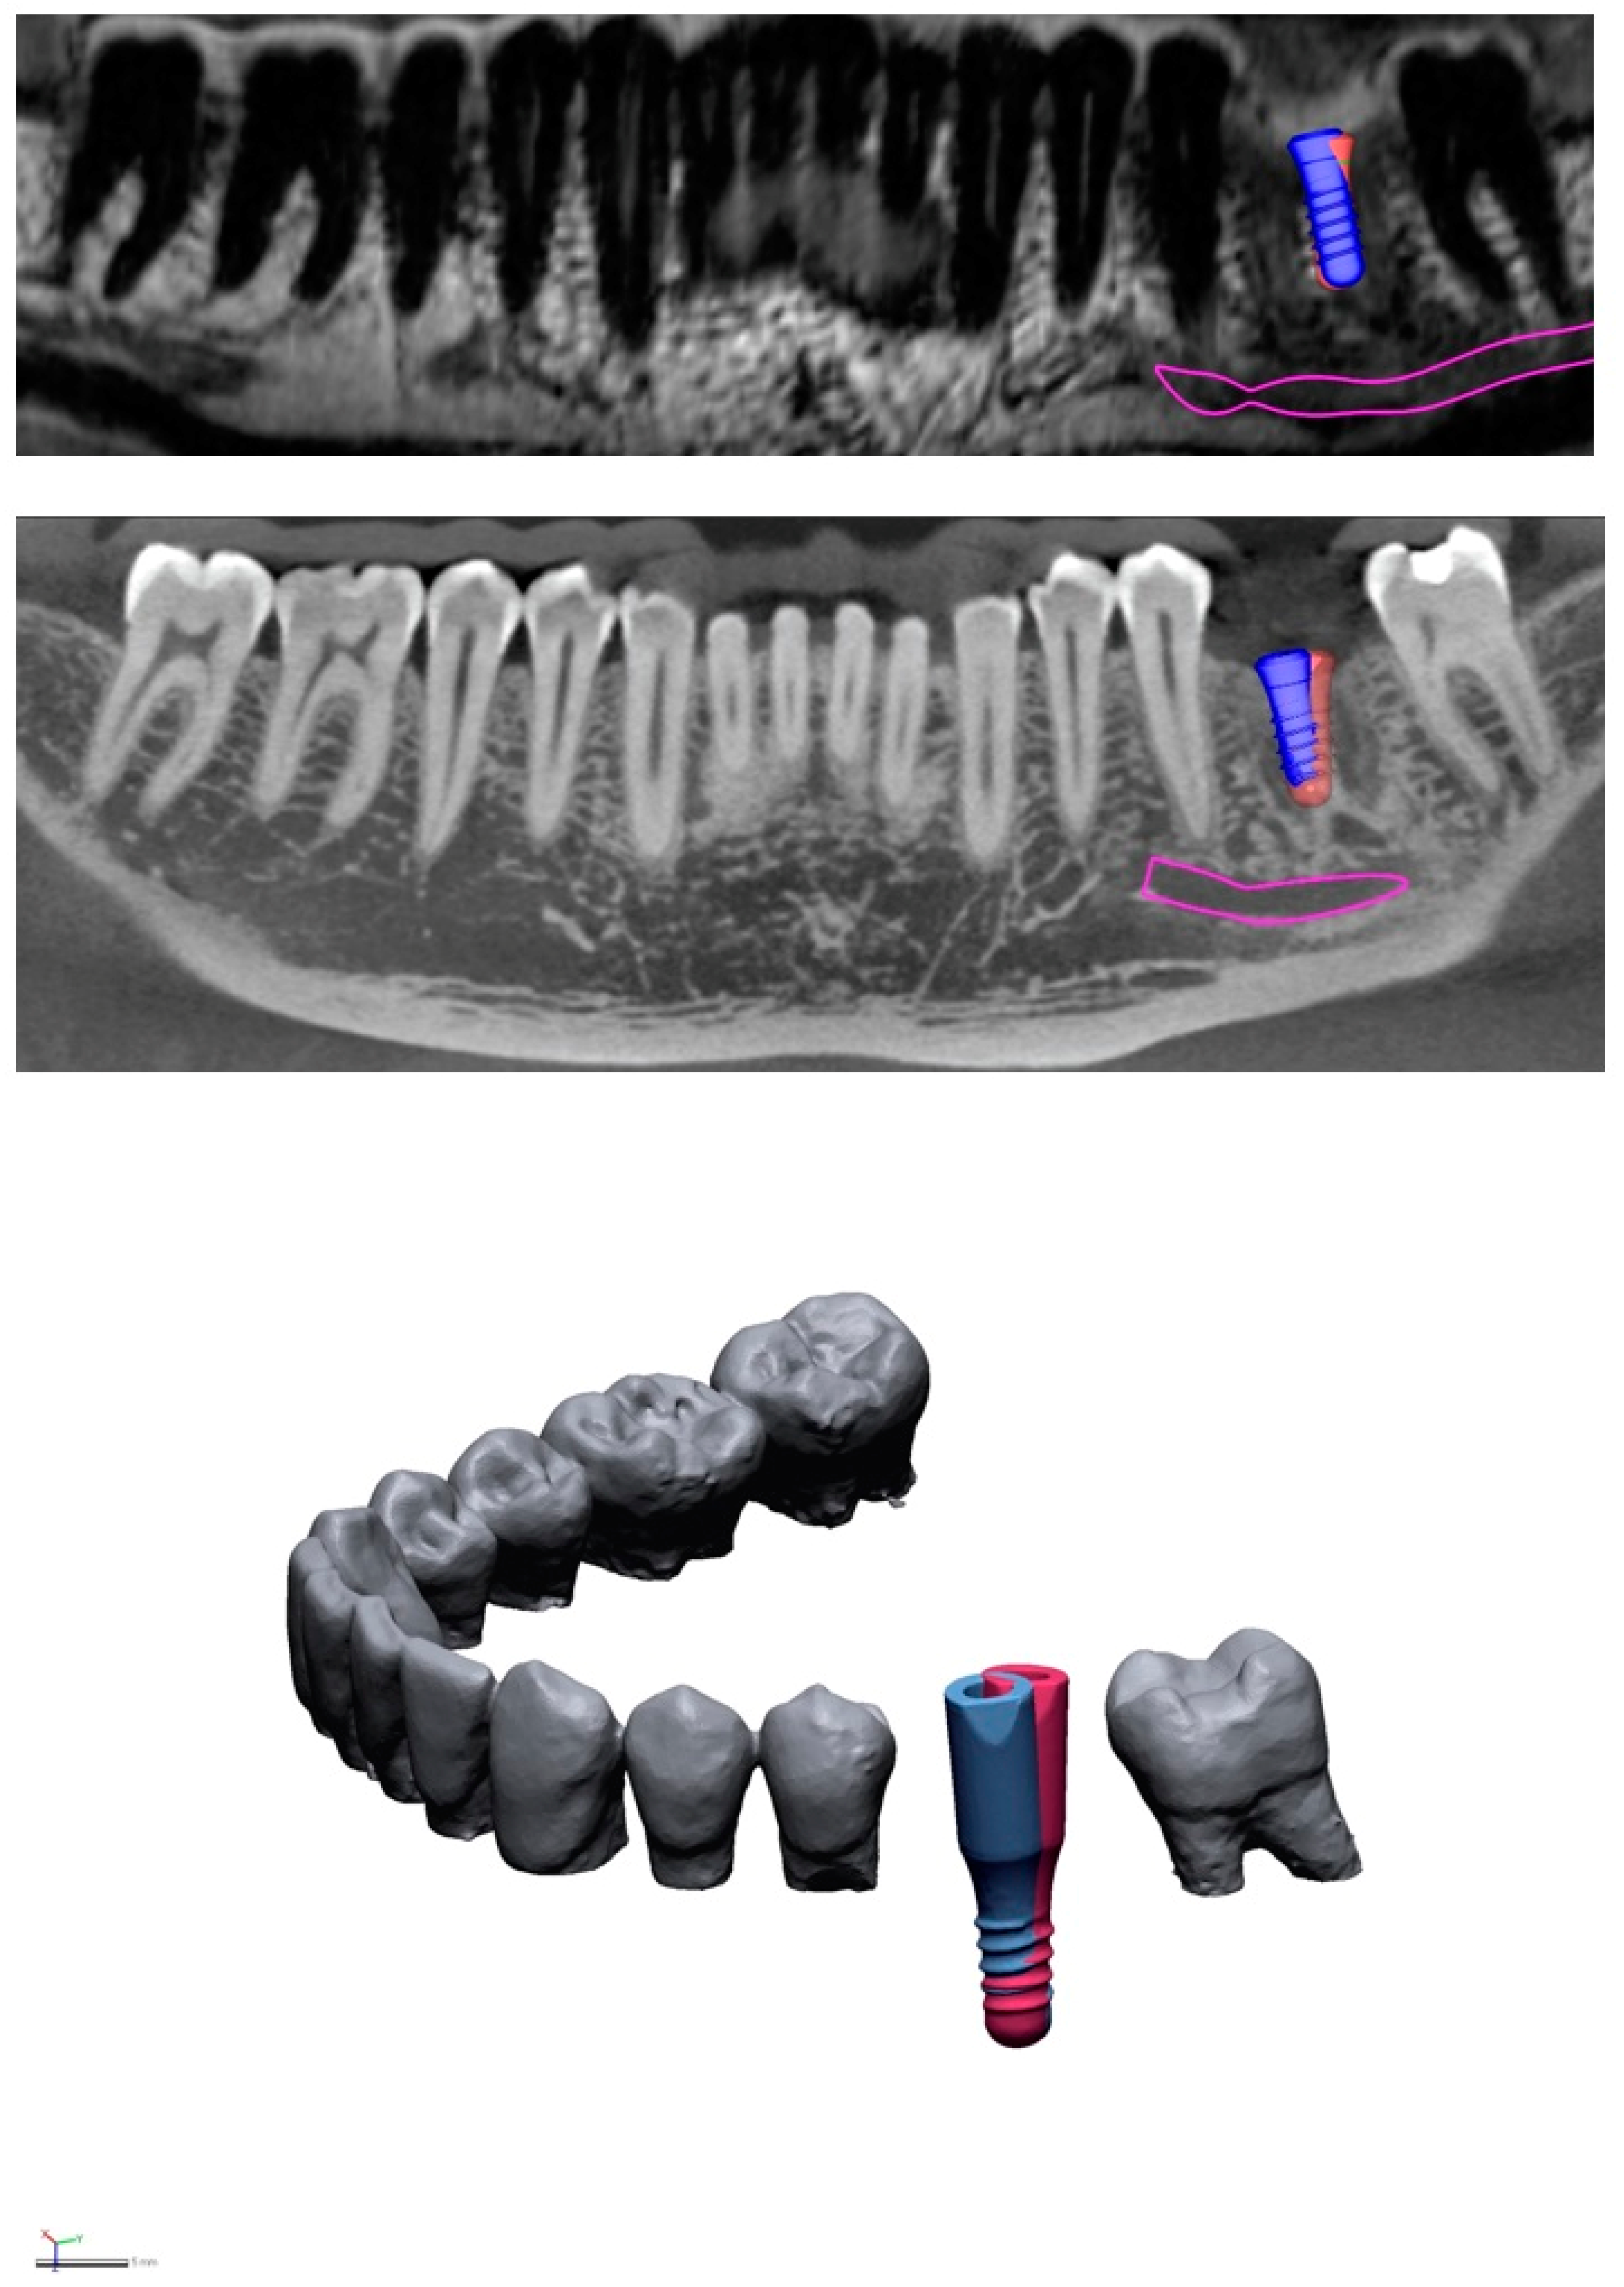

Let's delve into the science behind MRIs, explore the materials used in dental implants, and address any potential risks. Q: Why do I need to inform the healthcare provider about my dental implant for an MRI? A: Dental implants are made of metal and can interfere with the MRI machine.

The implants may cause some distortion in the images, but this can be minimized Whether you need a tooth replacement or are exploring missing teeth solutions, understanding how implants interact with medical imaging can help you make informed decisions about your oral health. Get MRI-safe dental implants with Smart Arches! At Smart Arches , we care deeply about your long-term wellbeing and take every aspect of your health into consideration

Can you have an MRI with Dental Implants? Prime Dentistry. Let's delve into the science behind MRIs, explore the materials used in dental implants, and address any potential risks. Undergoing an MRI (Magnetic Resonance Imaging) scan can raise concerns for patients with dental implants